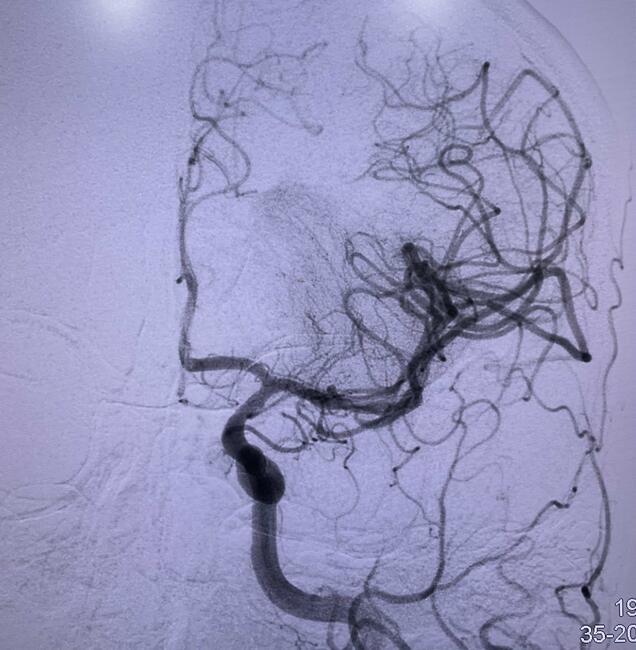

Further diagnostic workup included brain magnetic resonance imaging (MRI) and magnetic resonance (MR) angiography of intracranial vessels. The brain MRI revealed evidence of an acute infarct situated within the left middle cerebral artery (MCA) territory, affecting the left insular cortex as well as the adjacent frontal and temporal operculum (Figure 1). Additionally, the MR angiography depicted a cutoff in the M1 segment of the left MCA (Figure 2).

Promptly after admission, the patient received immediate treatment through intravenous thrombolysis with a dosage of 30 mg of tenecteplase. Subsequently, a mechanical thrombectomy procedure was conducted, employing a RED 72 reperfusion catheter (Penumbra). Following 2 passes of the catheter, a resilient clot was successfully retrieved. This intervention resulted in the complete recanalization of the MCA, leading to full perfusion of the entire left MCA territory (modified treatment in cerebral infarction score of 3, a successful recanalization). Notably, during digital subtraction angiography, an incidental finding revealed a shelf-like filling defect within the left carotid bulb, which was subsequently identified as a carotid web (Figures 3, 4, and 5).